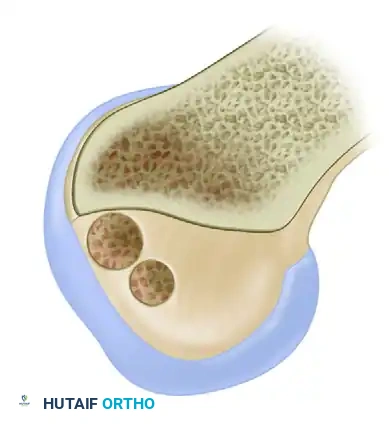

Patellofemoral pathology frequently coexists with ligamentous instability or presents as an isolated source of anterior knee pain. "Chondromalacia" refers specifically to the pathological softening, fibrillation, and degradation of the articular cartilage of the patella.

Modified Outerbridge (Insall) Classification

Arthroscopic evaluation of chondromalacia is graded to guide treatment:

- Grade I: Softening and swelling (blistering) of the articular cartilage.

- Grade II: Fragmentation and fissuring confined to an area ≤ 0.5 inches in diameter.

- Grade III: Severe fragmentation and fissuring involving an area > 0.5 inches in diameter (often described as a "crabmeat" appearance).

- Grade IV: Full-thickness erosion of cartilage down to exposed subchondral bone.